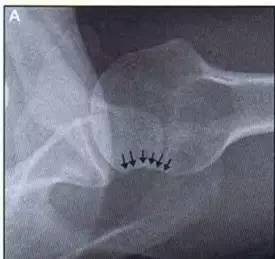

Hill-Sachs 损伤的 X 片(来源:Hill-Sachs Injuries of the Shoulder)

肩关节前脱位时发生的肱骨头后外侧凹陷性骨折,是经典的 Hill-Sachs 损伤(Hill-Sachs lesion);

而肩关节后脱位时发生的肱骨头前内侧凹陷性骨折,是反 Hill-Sachs 损伤(Reverse Hill-Sachs lesion/ McLaughlin lesion)。